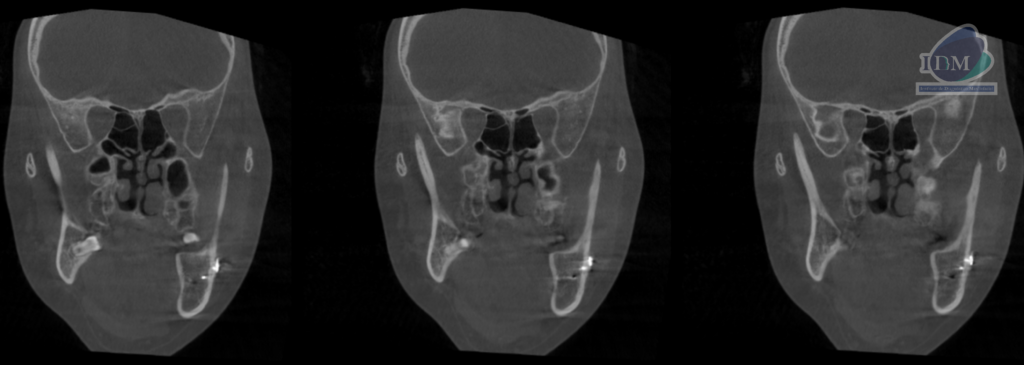

Así mismo en la tomografía volumétrica de haz se confirma una elongación por parte de la apófisis coronoides de lado derecho, extendiéndose sobre el borde superior del arco cigomático de ese mismo lado.

CORTES CORONALES

- Hiperplasia de apófisis coronoides de lado derecho.